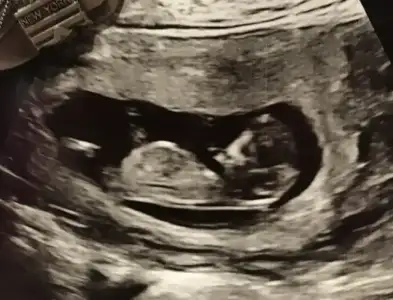

Merhaba. 11+2’deki USG icin cinsiyet tahmininizi alabilir miyim? İlk goruntu karindan usg, digeri vajinal usg. Tesekkur ederim.

C43296EA-BDBC-40E0-84B3-21D0955395DF.webp 5A258968-852F-4229-9D07-ABD4784CBBD3.webp